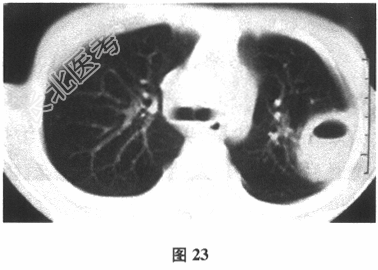

- [材料题] 患者男性,78岁,咳嗽、咳痰2周。既往有脑血管疾病史,否认高血压、糖尿病、冠心病史,否认慢性呼吸系统疾病史。胸部CT见图23。

- 多项选择题1.初步考虑患者的诊断是( )

A、支气管肺癌

B、肺结核

C、肺脓肿

D、军团菌肺炎

E、肺曲霉菌病

F、病毒性肺炎

G、肺转移癌